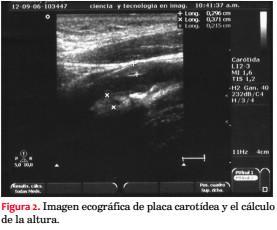

Los pacientes fueron subdivididos en cinco grupos según el grado de compromiso aterosclerótico carotídeo. Además de la obtención de datos convencionales, por protocolo se incorporó el score de placa carotídeo (SP)(30-32). El SP se obtiene mediante la sumatoria en milímetros (mm) de la altura de las placas carotídeas, constituyendo un dato numérico que permite cuantificar, reproducir y analizar estadísticamente los resultados, así como el seguimiento de los pacientes. En la figura 1 se muestra un esquema de su obtención, y en la figura 2 una imagen ecográfica real con la medición del SP. Placa significa una altura > a 1,5 mm(30-32). La caracterización clínica para cada uno de los cinco grupos se muestra en la tabla 2.